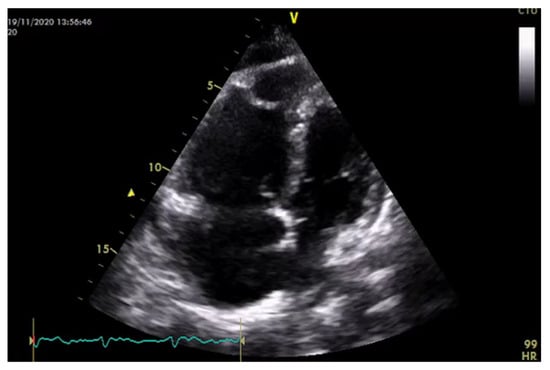

| Perfusion parameters | LVOT VTI and CI | A reliable quantitative parameter that truly reflects circulatory status and global end organ perfusion | LVOT VTI ≥ 18 cm CI ≥ 2.5 L/min/m2 |

| LVOTO | Its diagnosis leads to drastic changes in the clinical management | LVOTO < 30 mmHg | |